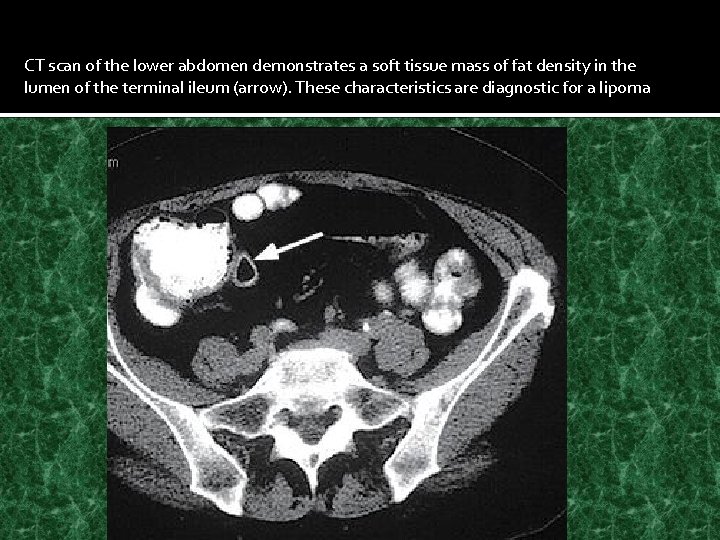

CT scan of the lower abdomen demonstrates a soft tissue mass of fat density in the lumen of the terminal ileum (arrow). These characteristics are diagnostic for a lipoma